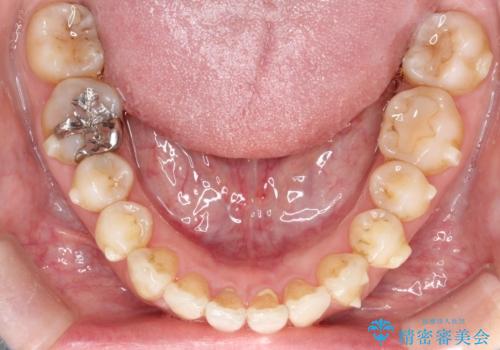

- 前歯の凸凹と、前突を主訴に来院されました。

インビザライン にて治療を行なっております。

治療期間中はゴムかけを行なってもらうことで、前歯を下げることができました。